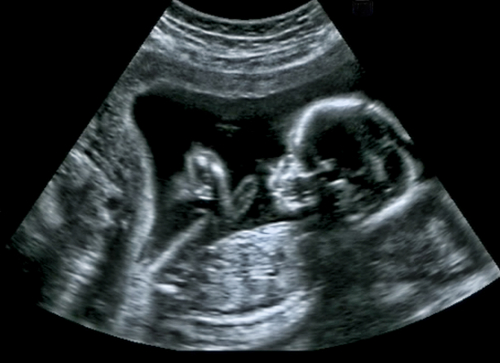

定期的に行う妊婦健診は、母体と胎児両方の健康状態を把握し、妊娠を適切に管理するために大切な機会です。妊婦健診をかかさず受診することが病気の早期発見・早期治療の鍵となります。りんご病の母子感染から引き起こされる胎児水腫についても、定期健診のエコーで早めに発見して適切な治療を受ければ影響を少なくすることができるかもしれません。忘れず受診を続けましょう。